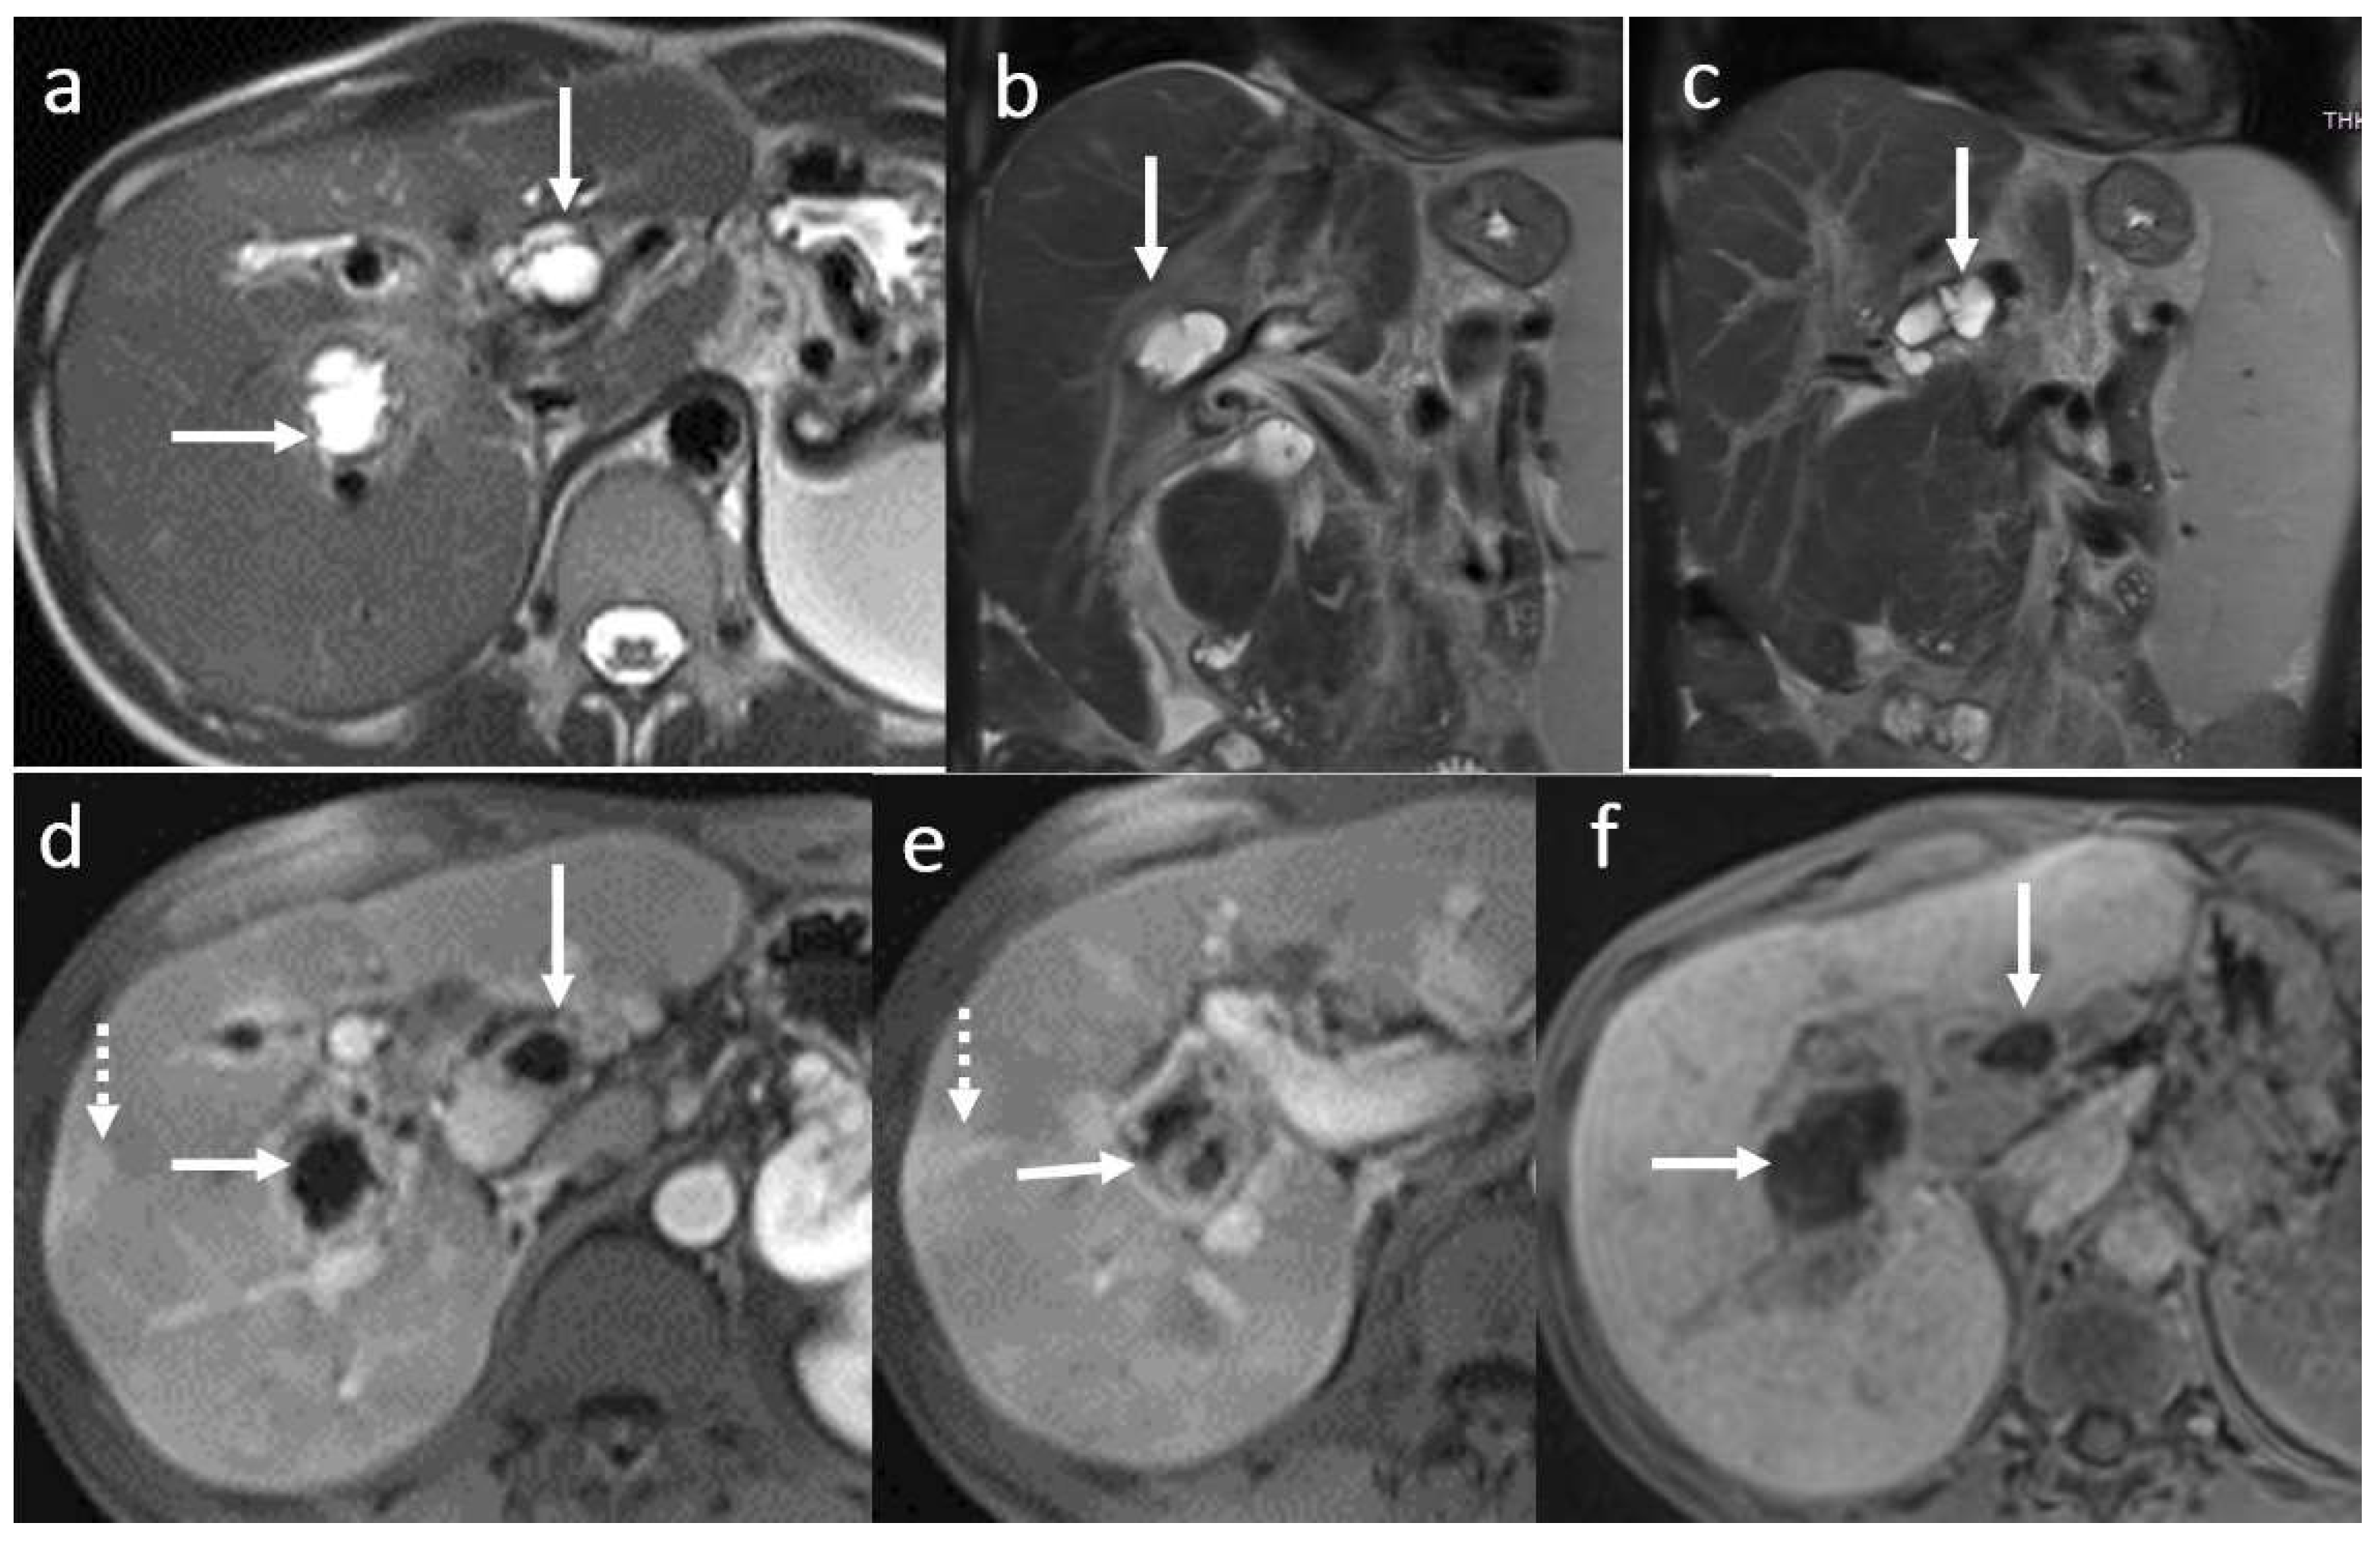

3.5. Biloma and Bile Leaks

3.6. Secondary Cholangitis

3.7. BT Lithiasis